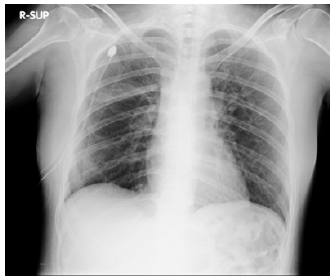

After ECG (normal sinus rhythm) and routine biochemical profiles (within normal limits) was subjected before to chest X-ray (large right-sided pneumothorax) and then to CT-scan to investigate secondary causes of pneumothorax which showed innumerable thin-walled cysts throughout both lungs (Figures 1,2) and angiomyolipoma in the left kidney.

Drainage (24 Fr) was placed in emergency and after three days the patient underwent to right video assisted thoracoscopy (Figure 3) with small wedge resection of the lower lobe where air-leak persisted (confirming the pathological diagnosis of LAM) and chemical pleurodesis with talc. After chest x-ray (two day after VATS) (Figure 4) showed complete lung re-expansion, we removed the drainage.

The patient was discharged the day after without noted post-operative complications. The patient was seen by her pulmonologist three months after the operation and her clinical status was stable without shortness of breath or chest pain. Therapy with sirolimus was started after pathological diagnosis of LAM (Figures 1-4).